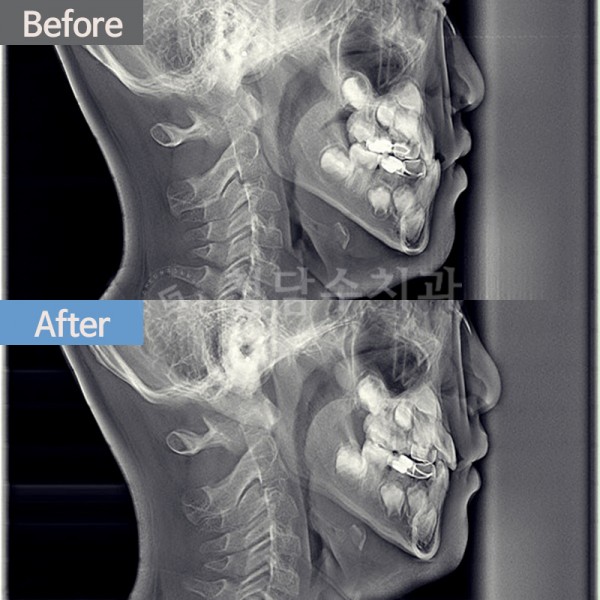

치아교정 어린이 교정

어린이 교정